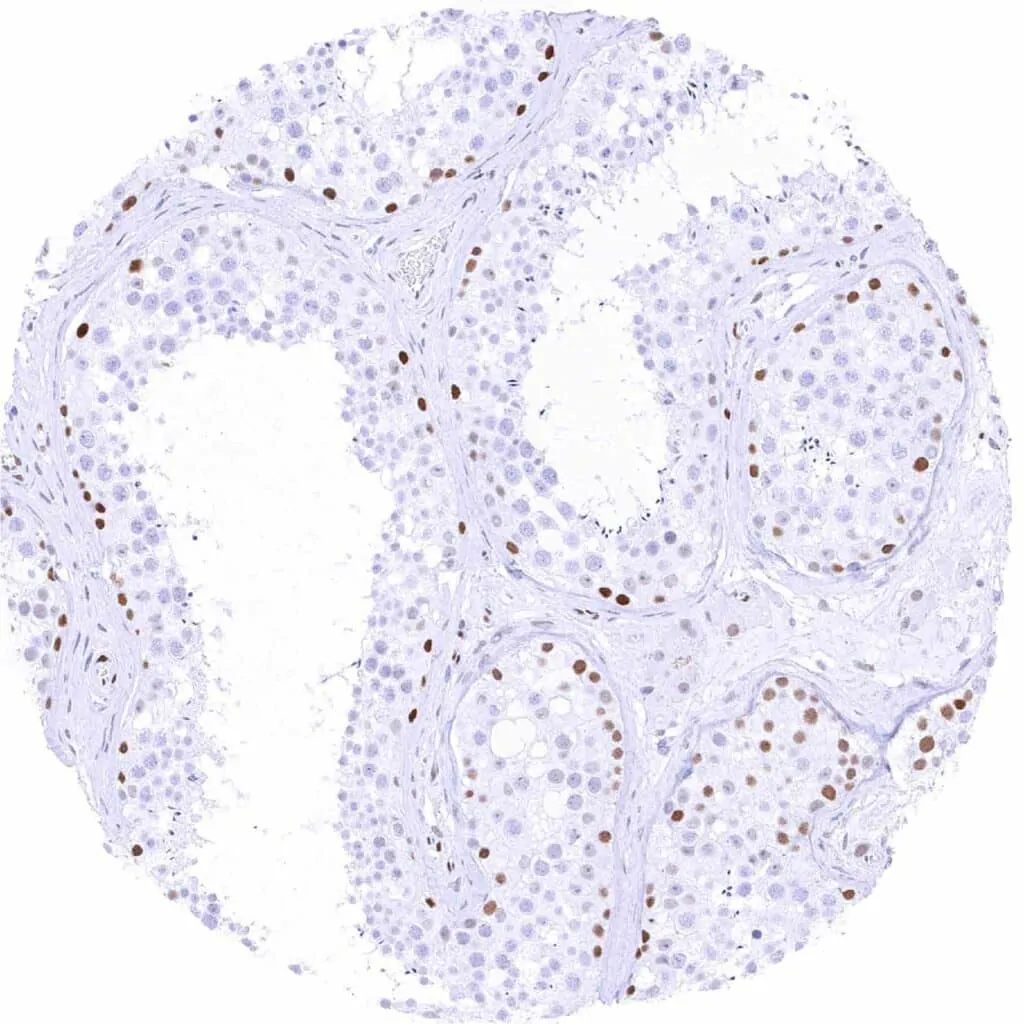

Testis – Moderate to strong TLE1 staining of spermatogonia